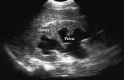

Figure 3

Perisplenic fluid.